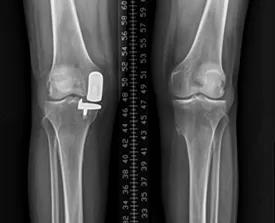

(二)膝骨关节炎单髁置换术

膝关节外科技术力量雄厚,科室配备医护人员30人,其中,主任医师5名,副主任医师3名,主治医师3名,住院医师4名,博士1名,硕士研究生4名。开放床位48张。该科擅长对膝关节严重创伤(包括股骨远端骨折、髌骨骨折、胫骨平台骨折等)、膝骨关节炎阶梯化治疗、保膝治疗、膝关节微创单髁置换术、全膝关节置换术、膝关节翻修术具有丰富的临床诊疗经验,追求微创、无痛、快速康复。对膝关节骨性关节炎采取阶梯化治疗方案,坚持中西并重、内外兼治的原则,取得满意的治疗效果。早期利用中医中药的传统优势,使用中医外治法,例如烫熨治疗、中药涂擦、雷火灸、中药塌渍等,同时辩证内服本院中药制剂及内服方药以及配合西药治疗,开展健康教育,运用运动疗法、物理治疗等辅助支持;中期开展软骨修复、截骨术、单髁置换术、髌股关节置换术等;对于终末期的膝关节OA采用全膝关节置换术。【膝关节外科主要特长】 (一)膝骨关节炎高位截骨术